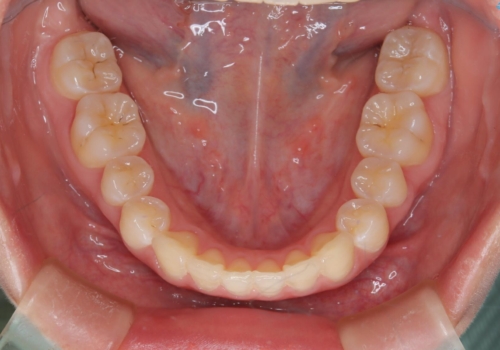

前歯のガタつきを治したい 翼状捻転マウスピース矯正

- 上顎前歯の突出、がたつき(翼状捻転)を主訴に来院されました。当院では総合歯科医療が可能であるため、矯正前処置として虫歯治療・歯周治療、親知らず抜歯を施行しました。その後、非抜歯かつ口元が出ないようなマウスピース治療を行いました。仕事柄、1日の装着時間が短くなってしまう時期もありましたが、患者様と相談しながら問題なく終了しています。